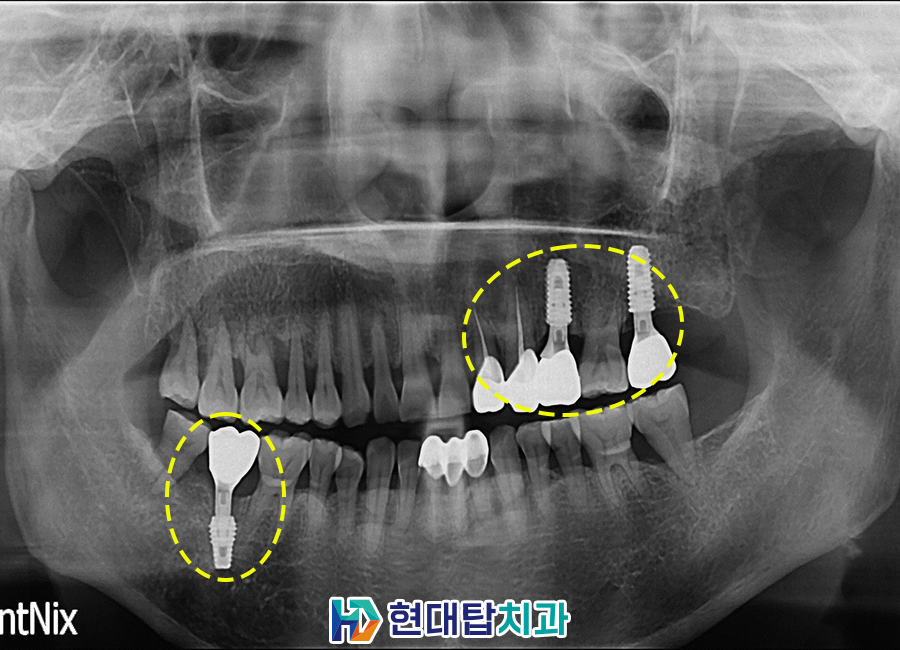

임플란트의 최종 보철물까지 완료한 모습입니다. 임플란트는 잇몸뼈와 융합이 가장 중요하기 때문에 식립 후 잇몸뼈와 인공치근이 단단하게 굳을 수 있는 기간을 기다려준 후 최종 보철물을 제작하여 보다 튼튼하고 안정적인 사용이 가능합니다. 환자분께서도 걱정 없이 편안한 식사에 만족도가 매우 높으셨습니다.